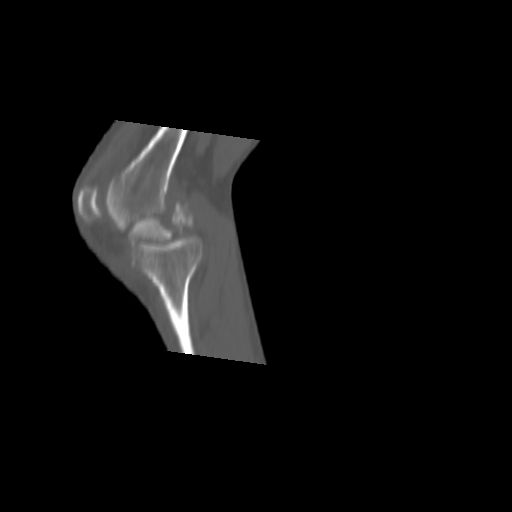

CT shows major bony fragments which are markedly rotated .With this amount of bony damage,you probably should attempt to get reasonably loooking knee with ORIF and thn if he needs a TKR due to pain a few years from now, then tleast you have something looking like a knee that you can replace rather than having to use revision knee for a primary TKR now. 4 weeks is not too long .what is the condition of soft tissues?

При внутрисуcтавных переломах трехмерные (3D) изображения, кроме красивого снимка, не дают полную информацию о состоянии отломков, самыми информативными являются корональные срезы на КТ и обычная длинная ренгенограмма конечности для сравнения оси конечности.

Фронтальные внутрисуставные переломы мыщельков бедра, так называемые Hoffa fracture, не частые, но встречающиеся переломы, в основном они связаны с травмой высокой энергией.

В зависимости от смещения рекомендуется сопоставление костных фрагментов с последующей жесткой фиксацией.

В вашем случае доступ будет медиальный, сопоставить развернутый медиальный мыщелок и фиксацию надо произвести в передне-заднем

направлении шурупами 4.5 мм в диаметре, углубив головку шурупов под хрящ, а поперечную фиксацию - межмыщелковыми шурупами. Желательно применить шурупы 6.3 мм в диаметре. Дополнительная Buttress technique пластина предотвратит перелом от скольжения.

Даже при сросшемся переломе мыщелка рекомендуется реконструктивная операция для предотвращения последующих варус или вальгус деформации.

Место образовавшего костного дефекта после разворота мышелка заполняется спонгиозной аутокостью. Костная пластика применяется даже

в свежем случае.

Под наркозом редрессация, ранняя разработка сустава после операции, нагрузка на конечность через 12 недель помогут удержать без коллапса

фиксацию и поможет больному восстановить функции конечности без артропластики коленного сутава.